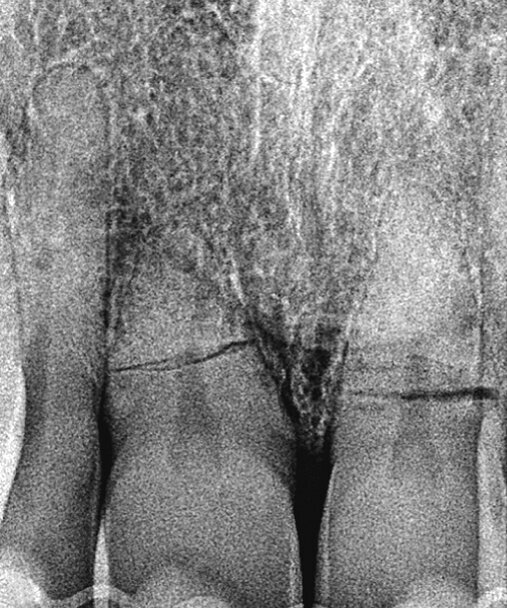

Pacijent u dobi od 66 godina doživio je traumu s posljedičnom frakturom korijena i palatinalnom dislokacijom zubi 11 i 21. Zubi su u okviru hitnog zbrinjavanja reponirani i splintirani (Slika 1.). Na pojedinačnoj rendgenskoj snimci zubi 11 i 21 uočava se intraalveolarni poprečni lom (Slika 2.). Prema aktualnim smjernicama takav lom u početku ne zahtijeva endodontsko liječenje ako se može isključiti da frakturna linija preko gingivnog sulkusa, odnosno parodontne pukotine komunicira s usnom šupljinom.

Slika 2. Početna situacija: Pojedinačne snimke zubi 11 i 21 s jasno vidljivim lomom korijena